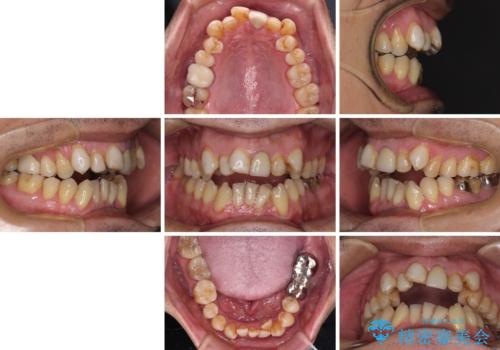

- 長年気になっていた口元を改善したいとのことで来院された患者様です。

外科手術を併用した矯正治療を検討するほどに隙間の空いた開咬と、顕著な叢生が認められました。

開咬の改善には、舌の突出癖改善のためにトレーニングを行いつつ、インビザラインでの矯正治療が大変有効ですが、上顎骨が下顎骨に対して前方位に位置しており、インビザライン単独で治療を行うよりは補助装置とワイヤー矯正で奥歯の咬み合わせを改善してから、開咬改善のためのインビザライン矯正治療を行うこととしました。

奥歯の銀歯は、土台の一部に抜歯が必要であったので、矯正治療の途中で抜歯してからオールセラミックブリッジによる補綴治療を行うこととしました。

外科処置は希望されなかったので、開咬の改善は限界があると事前にお話ししていたため、上下前歯が完全に接触する前に、もう十分改善したとのことで治療を終了しました。

インビザラインを毎日22時間しっかりと装着してくださったので、我々も驚愕するほどの治療成果が達成されました。